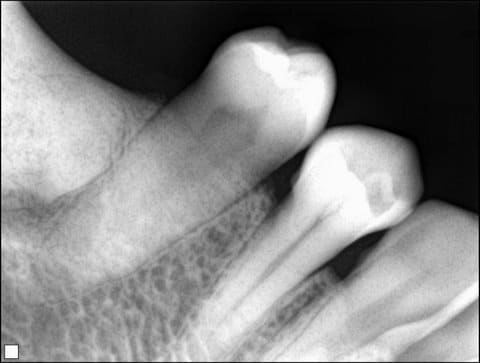

Une image radio du secteur 4. Femme de 40 ans. Aucun symptome particulier. Cela vous fait penser a quoi? On envoie chez le stomato ou pas pour explorer?

Dysplasie cémento-osseuse de type focale si le secteur 40 est seul touché.

La lésion devait exister probablement avant les avulsions mais a pu évolué.

si il existe d'anciens clichés, c'est intéressant.

pas de traitement à prévoir jusqu'à nouvel ordre.